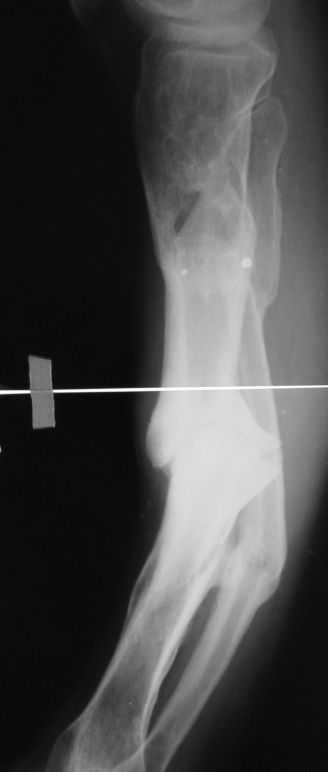

Уважаемые коллеги. Имеется вот такой псевдоартроз. Планируем БИОС tibia стержнем Chm, остеотомию малоберцовой и большеберцовой через зону псевдоартроза. Вопрос! Коррекцию лучше сделать одномоментно во время операции или дозированно в аппарате недели за 2-3, а потом nailing? И ещё делать нормо или с учетом вальгуса гиперкоррекцию?Заранее спасибо за советы!Митрофанов А.И. г. Курган

Одномоментно такой угол устранить трудно, сильно натянутся ткани по наружной поверхности голени. Может и стопа повиснуть. А что по второй проекции?

Мы бы сделали после остеотомии малоберцовой и аппаратной коррекции. Большеберцовую можно исправить за счет растяжения пседартроза. Можно и сделать поперечную остеотомию чуть дистальнее несращения, в этом случае будет удобный вход в периферический отломок. А зону несращения пройти разверткой просто по прямой. Схема в приложении.

Александр Николаевич, вечер добрый! Извиняюсь за отсутствие второй прекции. там тоже ещё та деформация! Дозировано исправлять - не уверен что идиально получится выставить по оси дистальный отломок, а смещение даже на кортикал, не влияющие на консолидацию в аппарате, при формировании канала и введении стержня в условиях вальгуса и рекурвации, ну не знаю. Второй вариант, о котором и вы говорите, думаю более предпочтителен. А если делать остеотомию дистальнее ложняка, то что помешает одномоментно откоррегировать? Парез и при аппаратной коррекции с той же долей вероятности может быть.